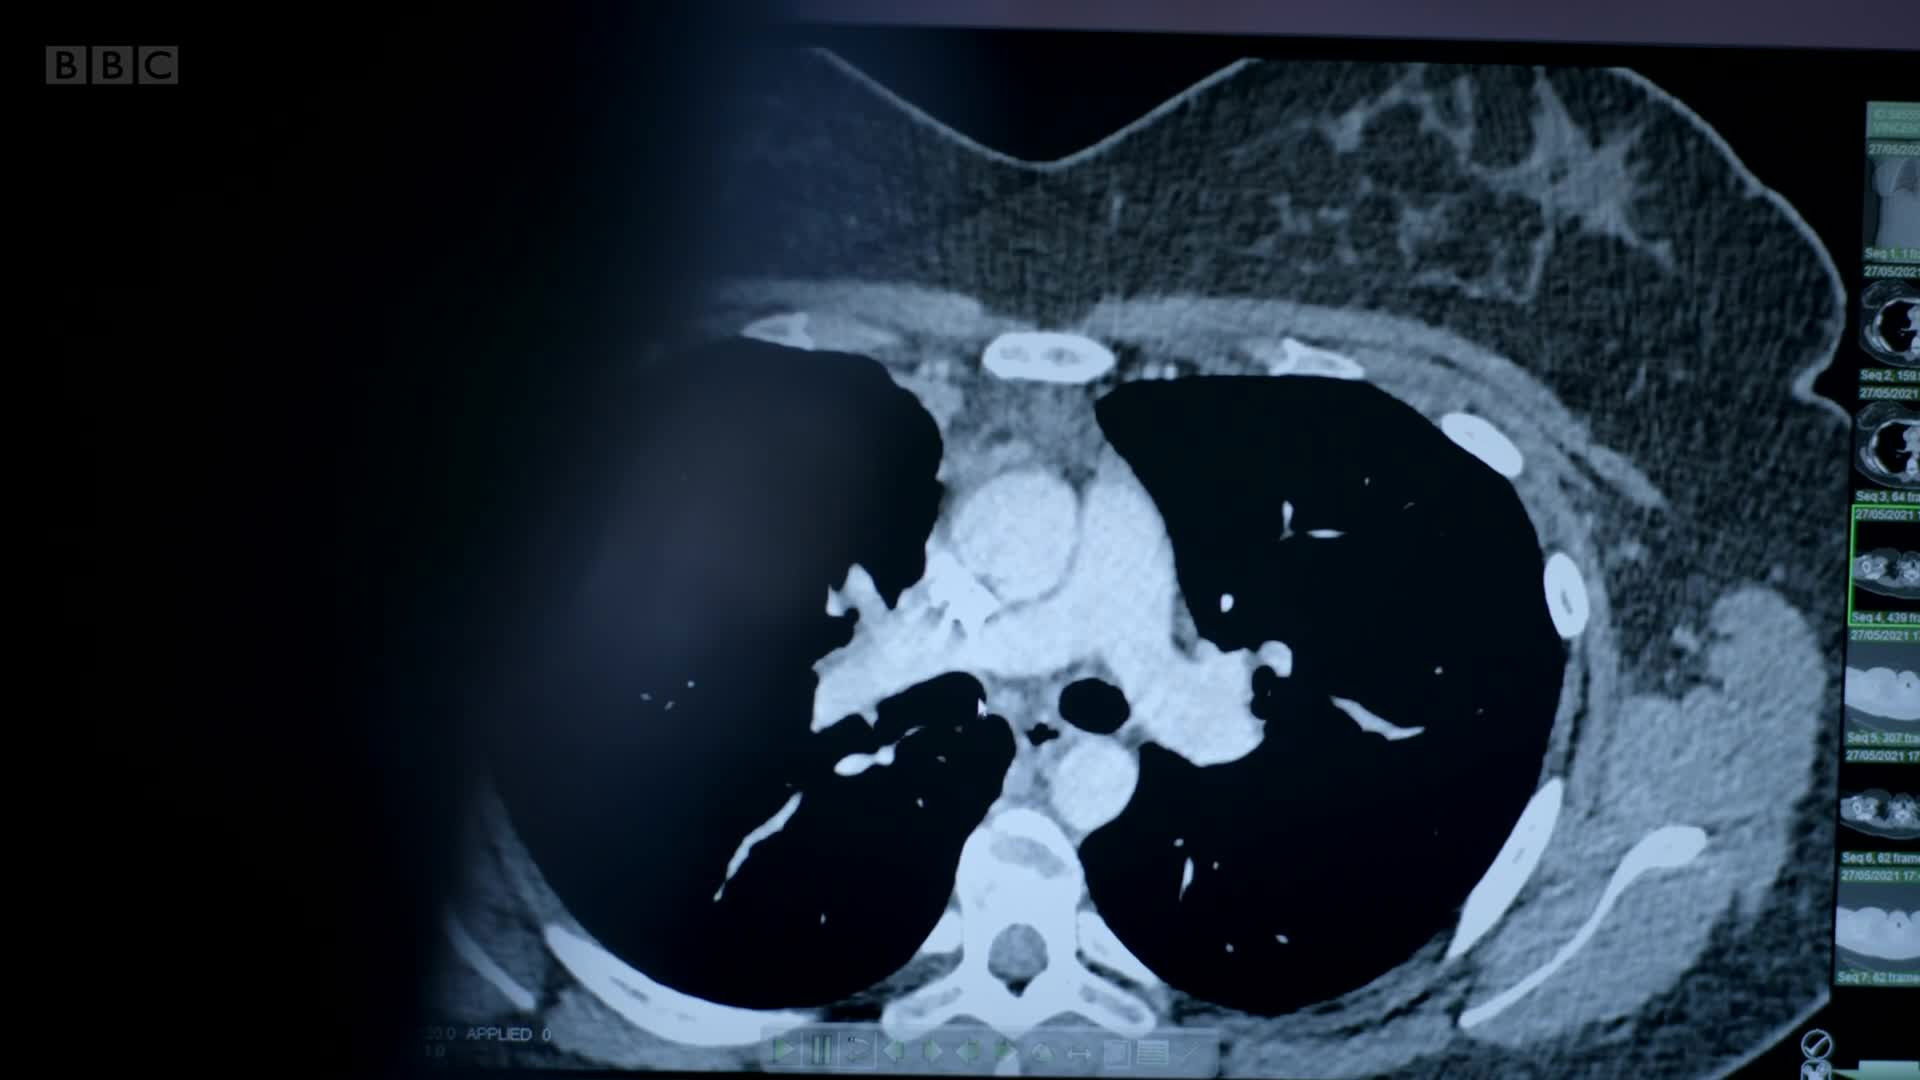

Operations where even a small mistake is catastrophic. Surgeons at Addenbrooke’s and Royal Papworth hospitals remove a life-threatening tumour and repair a young patient’s aorta.

Surgeons at Royal Papworth and Addenbrooke's hospitals must put their patients back together again after removing life-threatening lung and facial tumours.